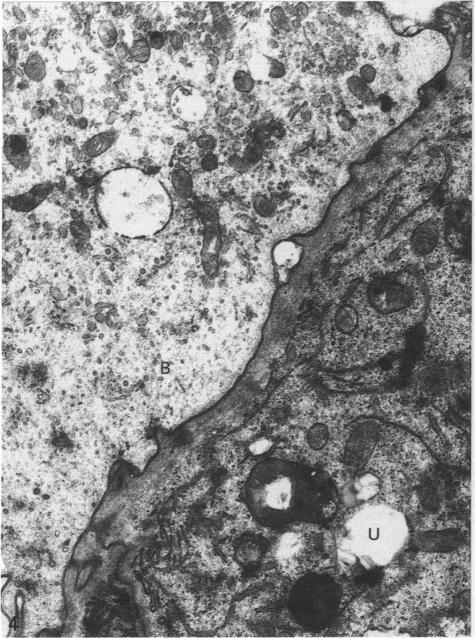

In the goat conceptus individual intra-epithelial trophectodermal binucleate cells first appear 18 days post coitum and their incidence rapidly increases where the trophectoderm is apposed to the caruncular and intercaruncular sites of initial attachment to the uterine epithelium. Special staining techniques reveal that these cells, when mature, contain prominent Golgi bodies and numerous characteristic granules. Our evidence shows that at 19 days post coitum the binucleate cells migrate to the microvillar junction and fuse with individual uterine epithelial cells to form hybrid feto-maternal trinucleate cells. It is proposed that subsequent continued binucleate cell migration and fusion with trinucleate cells produce the syncytial plaques typical of the remainder of pregnancy. It is further suggested that the fusion is important in facilitating the delivery of the characteristic granules to the base of the uterine epithelial layer with subsequent exocytosis of their contents into maternal tissue.

在山羊孕体中,上皮内滋养外胚层双核细胞最早在交配后18天出现,在滋养外胚层与子宫上皮最初附着的肉阜和肉阜间部位相对处,其发生率迅速增加。特殊染色技术显示,这些细胞成熟时含有明显的高尔基体和许多特征性颗粒。我们的证据表明,在交配后19天,双核细胞迁移至微绒毛连接处,并与单个子宫上皮细胞融合形成杂种胎儿-母体三核细胞。有人提出,随后双核细胞持续迁移并与三核细胞融合,产生妊娠剩余时间典型的合体斑块。进一步表明,融合对于促进特征性颗粒输送至子宫上皮层底部并随后将其内容物胞吐到母体组织中很重要。